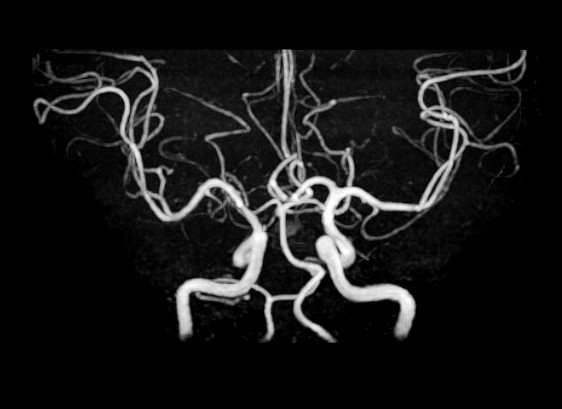

脳MRI・MRA検査

MRI(磁気共鳴画像)とMRA(磁気共鳴血管画像)を用いて、脳の断面や血管の状態を詳しく確認する検査です。

痛みや放射線被ばくの心配がなく、寝ているだけで脳の健康状態を調べることができます。

自覚症状のない小さな病変の早期発見を目指します。

脳MRI・MRA診断画像3

この検査でわかること

• 脳出血の原因となる血管の異常

• 脳腫瘍の有無

• 加齢や認知症に伴う脳の変化

• 自覚症状のない小さな脳梗塞の跡